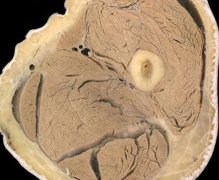

实拍:开颅手术全过程

实拍:开颅手术全过程...(63)人阅读时间:2018-06-13